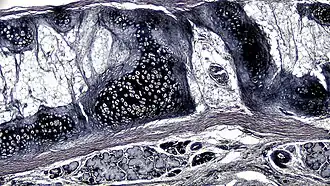

A cross section of mammalian elastic cartilage

Lateral side of the auricle

Elastic cartilage is histologically similar to hyaline cartilage but contains many yellow elastic fibers lying in a solid matrix. These fibers form bundles that appear dark under a microscope. The elastic fibers require special staining since when it is stained using haematoxylin and eosin (H&E) stain it appears the same as hyaline cartilage.[3] Verhoeff van Geison stains are used (giving the elastic fibers a black color), but aldehyde fuchsin stains, Weigert's elastic stains, and orcein stains also work.[3] These fibers give elastic cartilage great flexibility so that it is able to withstand repeated bending. Similarly to hyaline one or multiple chondrocytes lie between the spaces (or lacunea) in the fibres.[2] The chondrocytes only make up 2% of the tissue's volume.[2] Chondrocytes and the extracellular matrix are contained in an outerlayer named the perichondrium[2] (which is a layer of dense irregular connective tissue that surrounds cartilage which is independent of the joint).[3] It is found in the epiglottis (part of the larynx), and the pinnae (the external ear flaps of many mammals). Elastin fibers stain dark purple/black with Verhoeff's stain.